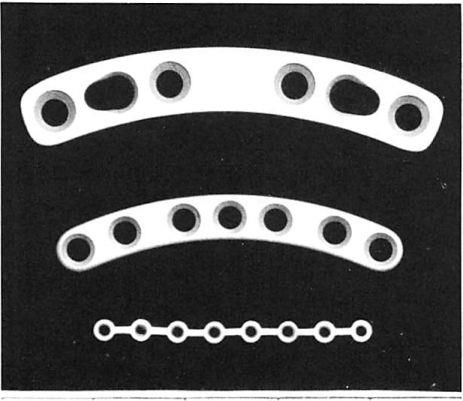

The microsystem used in this patient series has been the one designed by Luhr [12] (Howmedica, Rutherford, NJ). It is manufactured from vitallium (cobalt-chromium-molybdenum alloy). This system uses self-tapping screws having a cortical pitch (thread spacing) of only 0.3 mm and there-fore allowing use in extremely thin bone. Screw diameter is 0.8 mm. Plate thickness is 0.5 mm, with holes spaced at 4-mm intervals. The holes are joined by a straight connecting bar that allows three-dimensional plate bending without hole distortion. This size represents an —50% reduction in scale of most commercially available minisystems. Plates from the Luhr mandibular system, minisystem, and microsystem are presented for comparison in Figure 2.

Fig 2. Plates from (top to bottom) the Luhr mandibuJar system, minisystem, and microsystem.

Fig 2. Plates from (top to bottom) the Luhr mandibuJar system, minisystem, and microsystem.